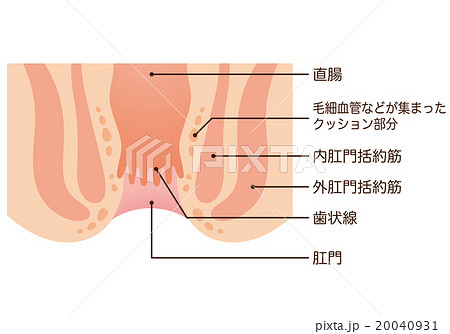

おしりの構造と病気 森外科医院 日本大腸肛門病学会認定施設 日本臨床肛門病学会認定施設 岐阜県大垣市で肛門科をお探しの方は肛門専門病院の森外科医院までご相談下さい

医療法人明信会 今泉西病院 裂肛の話

肛門外科 外科 診療科 部門紹介 外来受診される方 宇治武田病院 武田病院グループ

肛門 直腸の構造断面図イラスト 人体 医療 イメージマート

肛門 断面図 直腸の写真素材

肛門 断面図のイラスト素材